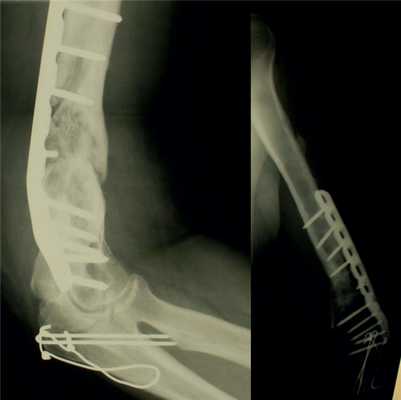

Послеоперационное течение без осложнений, проводили регулярные перевязки с обработкой кожи вокруг стержней и спиц растворами антисептиков и сменой асептических повязок. Швы вокруг стержней сняты через 8 дней после операции, пациентка выписана на амбулаторное лечение с рекомендациями по дальнейшему восстановительному лечению. Движения в левом локтевом суставе перед выпиской из стационара показаны на рис. 4. Рисунок 4. Рентгенограммы больной П. после остеосинтеза левой плечевой кости спице-стержневым аппаратом.

После консолидации перелома через 71 день произведен демонтаж аппарата (рис. 5). Рисунок 5. Рентгенограммы больной П. после остеосинтеза левой плечевой кости спице-стержневым аппаратом. Движения в левом локтевом суставе после демонтажа аппарата от 0 до 128° (рис. 6). Рисунок 6. Внешний вид больной П. после демонтажа аппарата (объем движений в левом локтевом суставе от 0 до 128°).